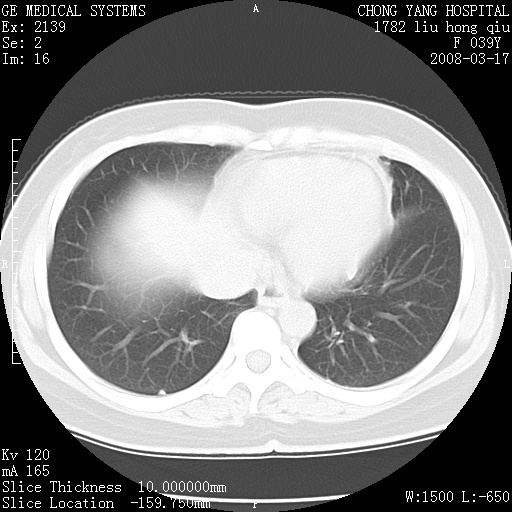

以下是引用yangxue121在2008-5-31 20:24:00的发言:[br]考虑多发胸膜间皮瘤[br]左侧少量胸腔积液[br]肝脏密度不均

以下是引用王仕学在2008-5-31 20:10:00的发言:[br]考虑胸膜间皮瘤。

以下是引用长城干红在2008-5-31 21:42:00的发言:[br]肝脏密度不均,建议增强扫描,胸膜下多发结节,考虑为胸膜来源的原发肿瘤或转移瘤。